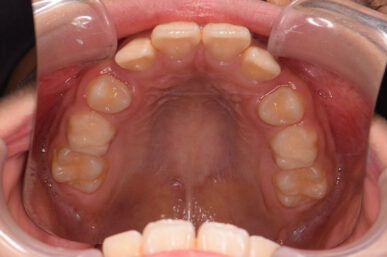

• Before

治療開始が遅くてこのままでは犬歯の生えるスペースが不足していて八重歯になるところでしたが、アライナー矯正で素早く歯を動かして犬歯が生えてくるスペースを作ることで八重歯にならずに済みました。

八重歯のケースは永久歯の抜歯が必要になることもありますが、避けることができました。

矯正後は永久歯がすべて生えるまでは予防歯科で歯の生え代わりと機能を管理します。